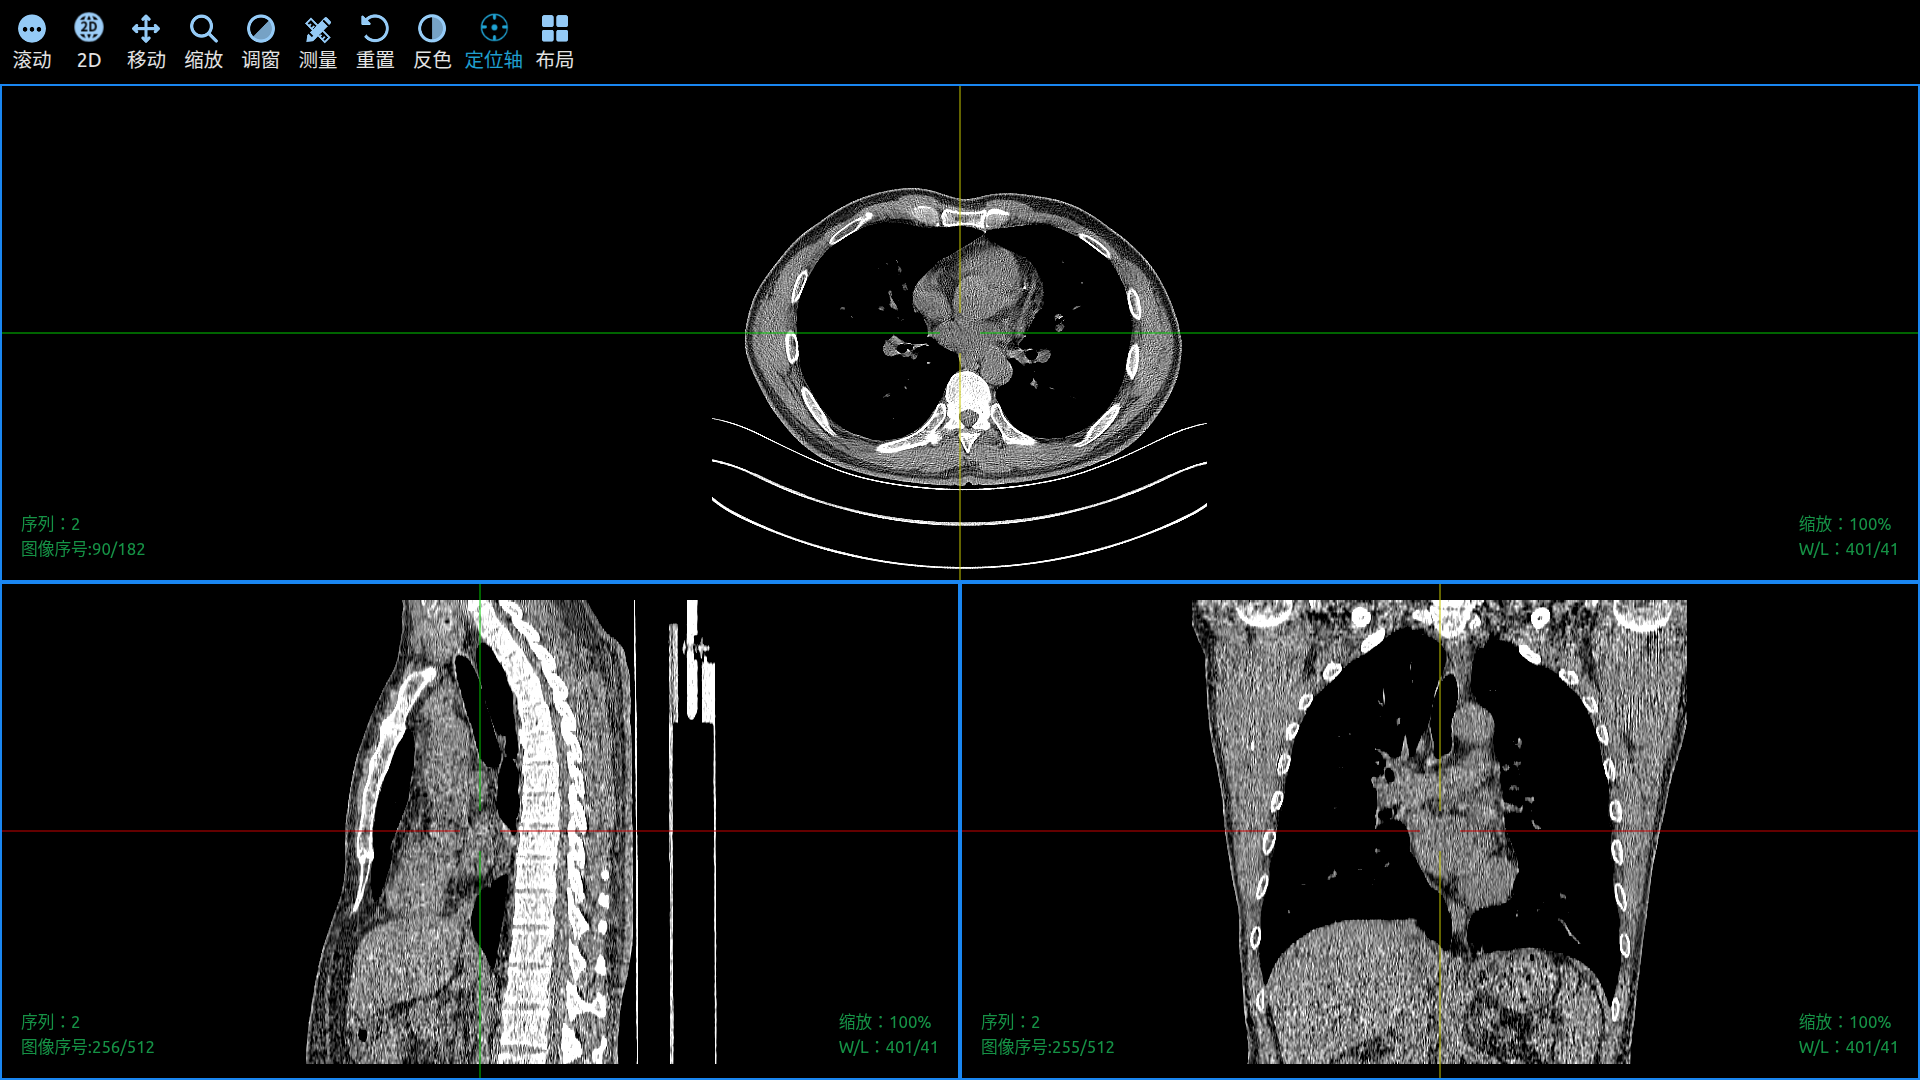

Use Cornerstone3D to View DICOM Images in a Web Browser.